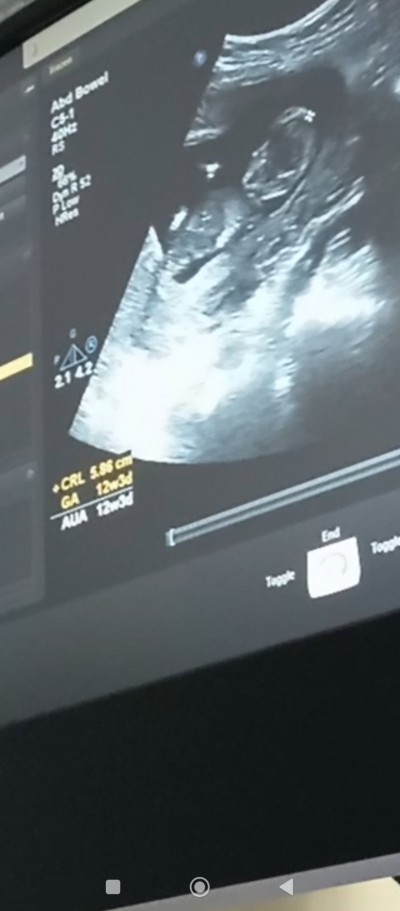

Kızlar 12+6 olan varmı benimle aynı gün. Cinsiyet sağlık. Nasıl.  Merakliyiz bekleyisteyiz  muabbetimiz bol olsun bakalım cinsiyetleri mız aynı olan varmı tahmin yapın lutfen

image

Gebelik haftası 12+6